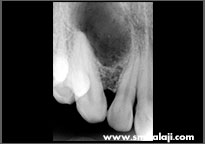

X-ray showing cyst lesion in upper jaw right side

Radiovisuograph showing cyst lesion